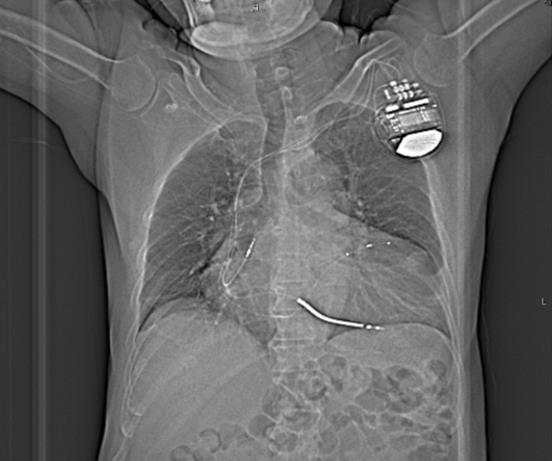

“蒋医生,你救救我,我再也不想感受这种‘雷刑’般的痛苦了。”浙江大学医学院附属邵逸夫医院心内科主任医师蒋晨阳见到患者张先生(化名)时,注意到这个身材魁梧的男人说话轻声细语,仿佛连大气都不敢出。仔细询问得知,张先生在两年前植入了心脏复律除颤器(ICD),但近一个多星期除颤器频繁放电,令他苦不堪言。

视觉中国供图

当地医院在详细评估后,为张先生植入了心脏除颤器,一旦出现危及生命的恶性心律失常,ICD会放电,终止心律失常,相当于在心脏发生了“电路短路”时,让心脏“重新启动”,同时配合口服药物治疗,尽可能减少室速的发作,延缓心脏病的进展。